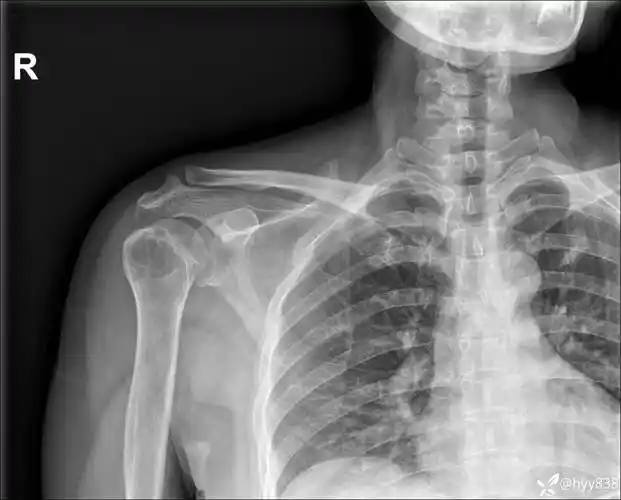

中年女性,发现右肩关节占位2天.有特征,有细节---(有结果)